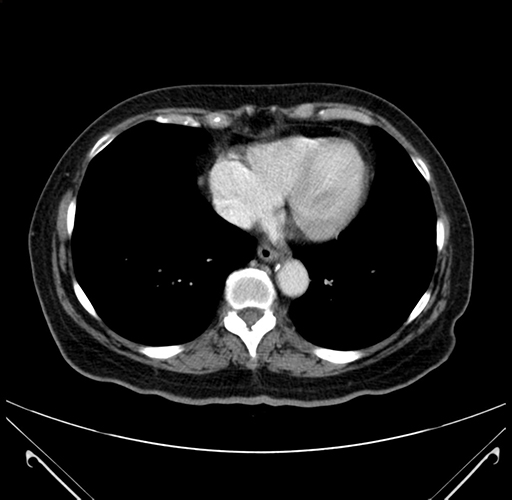

Pre-Chemo: Axial Venous

Axial Venous